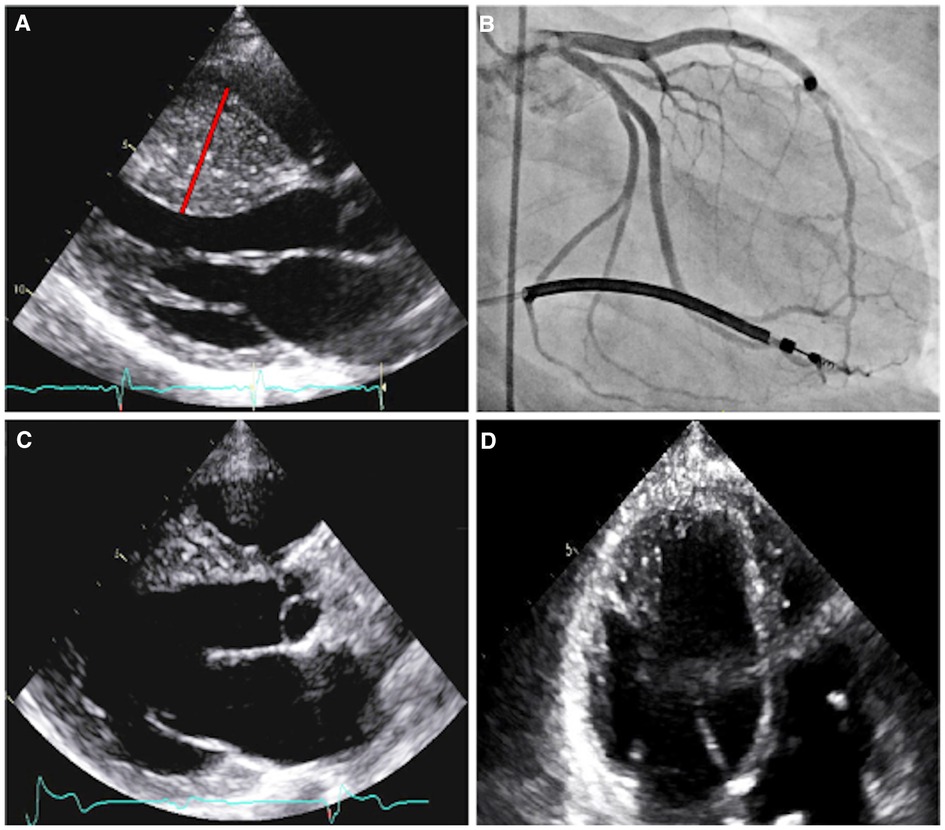

Patient A was initially referred for cardiac evaluation when she experienced a sudden out-of-hospital cardiac arrest at age 18. She was swing dancing with friends when she suddenly lost consciousness and was found to be pulseless. Bystander cardiopulmonary resuscitation was performed for eight minutes. On-site automatic external defibrillator advised no shock. She regained full neurological function during hospitalization with a hypothermic protocol. Serial 12-lead electrocardiograms (ECGs) demonstrated left ventricular hypertrophy with ST-T depression in the anterolateral leads, with an initial QTc interval of 510 msec that normalized throughout the course of hospitalization. Transthoracic echocardiography revealed HCM with massively hypertrophied left ventricular septum (33 mm) with a reverse curve septal contour (Figure 2A). There was no outflow tract obstruction at rest or with Valsalva maneuver. She underwent single-lead implantable cardioverter-defibrillation (ICD) placement and was started on metoprolol succinate 25 mg daily.

Figure 2. Imaging of patient A. Parasternal long axis echocardiogram prior to septal myectomy (A). The interventricular septum has reverse curve morphology, with a septal thickness measurement of 33 mm (red line) during diastole and a patent left ventricular outflow tract. Right anterior oblique caudal angiogram with prominent myocardial bridging of the large first and second septal perforators (B). Parasternal long axis echocardiogram, status-post septal myectomy (C). Four-chamber echocardiogram, with increased apical cavity size following septal myectomy (D).

Coronary angiography revealed marked myocardial bridging of large septal perforators (Figure 2B and Supplementary Video S1). She ultimately underwent coronary artery unroofing and extended septal myectomy through combined transaortic and transapical approaches to improve diastolic function and debulk her arrhythmogenic substrate (Figures 2C, D). Pathology demonstrated histological features consistent with HCM, including moderate to marked myocyte hypertrophy, mild to focally moderate myocyte disarray, and mild to focally moderate interstitial fibrosis. Flecainide was discontinued and sotalol (120 mg twice daily) was resumed on post-operative day four.